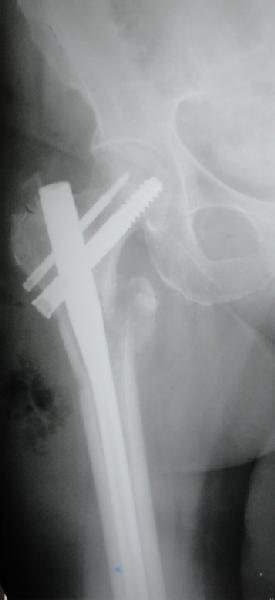

Фиксация * reversed obliquity* подвертельных переломов - дело непростое.

На мой взгляд, причиной телескопирования явилось несоответствие диаметра гамма нэйл с диаметром канала подвертельного отдела бедра: обратите внимание на величину протрузии шеечного винта и величину медиализации дистального фрагмента - они одинаковы, смещение или телескопирование фрагментов происходило до того момента, пока гамма нэйл не упёрся в медиальный кортекс и образовалось пространство между латеральным

кортексом и латеральной поверхностью гвоздя.